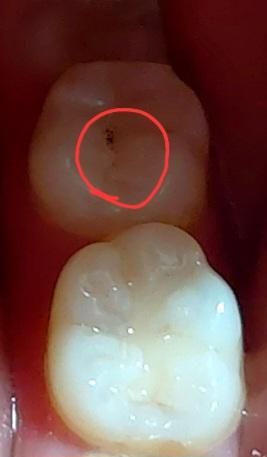

어금니에 까만점이 생겼는데 착색일까요...

충치인지 착색인지 모를 까만점이 갑자기 생겼어요.... 어제 오늘 단 거랑 탄산을 많이 먹었고 양치도 늦게 하긴 했는데 솔직히 착색이라고는 전혀 안 믿겨지구요...

충치란게 만성으로 진행되는 질환이기 때문에 어제는 없던것이 오늘 갑자기 생기거나 하지는 않습니다. 갑자기 생겼다면 착색일 가능성이 높고, 블루베리나 포도같은 것을 드시면 껍질이 끼어서 충치처럼 보일 수도 있어요. 그리고 사진이 선명하지 못해서 대충 위치나 색상으로만 봤을 때는 이미 떼워져있는 재료의 위가 까만 것 같은데 충치라면 레진의 하방이나 경계부위에 생기지, 재료에는 충치가 생기지 않습니다. 혹시 그 부분이 레진이 깨져나가서 홈이 있다면 충치일 가능성이 높습니다.

사진으로 보아서는 정확히는 알 수 없습니다. 하지만 경험적으로 보아서는 단순한 착색이 아닌 충치일 가능성이 큽니다. 물론 정확한 판단을 위해서는 다른 각도의 사진 뿐만 아니라 x-ray 등을 촬영해보아야 합니다. 사진상으로 보이는 부분보다 충치가 깊을 수도 있으므로 가까운 치과 방문 후 평가를 받고 빨리 치료하는 것이 좋습니다.

사진이 어두워서 명확히 보이지는 않으나 착색 가능성보다는 우식이나 이물질이 껴서 다음과 같이 보이는 것으로 추정됩니다. 근처 치과 내원하셔서 검사 받아보시기를 바랍니다.

까만점은 충치로 보여집니다. 치과에 내원하여 확인하면 좋을것같습니다. 건강하세요.